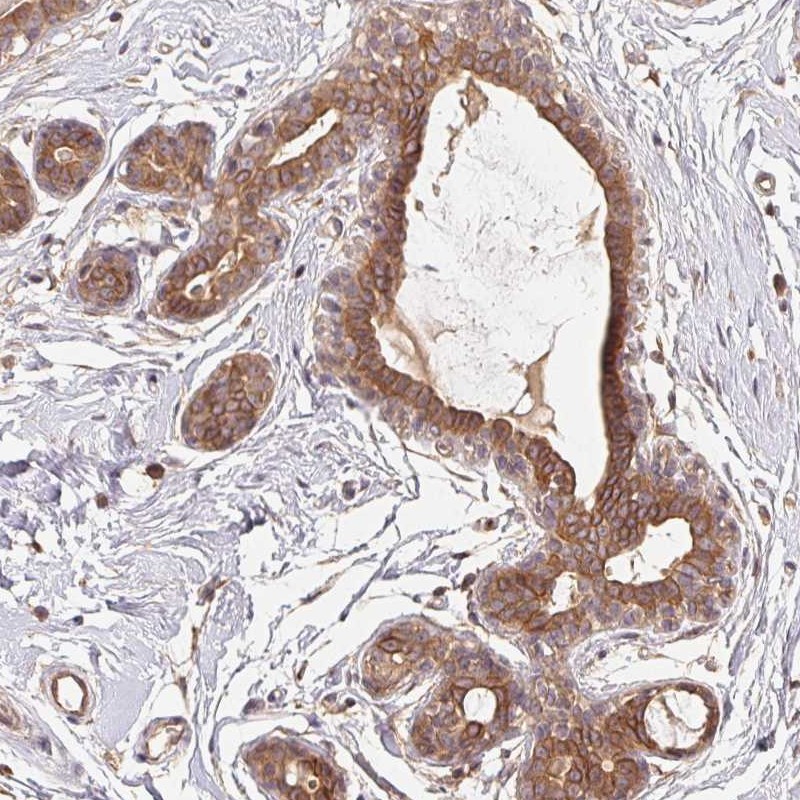

Immunohistochemical staining of human breast shows strong membranous and cytoplasmic positivity in glandular cells.